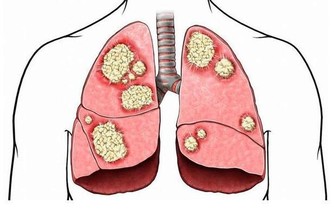

通常情況下,胃粘膜會很快修復來修復已破潰的組織,但假如經常、反複使胃粘膜遭受不良刺激,頻繁增生、修復,日積月累,就容易癌變。

大型流行病學表明,胃癌、冠心病、腦卒中、骨質疏鬆等許多疾病,都和吃太鹹有關。